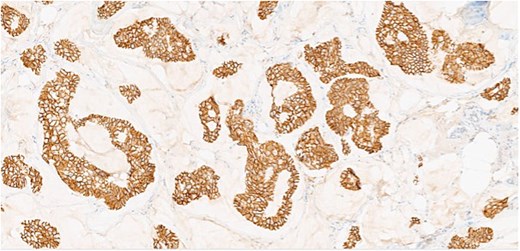

Herein, we present a 75-year-old man who, having been referred to our service with an inguinal hernia, raised concern about a palpable mass present in his right axilla. The main differential on initial examination was that of a simple epidermoid cyst, and consent was obtained for its removal during his elective hernia repair. Subsequent histology however, revealed a well differentiated MAC. There was extensive involvement of the deep and superficial reticular dermis (Figs 1and 2). Lymphovascular invasion was present. Sweat glands were focally involved by the carcinoma. The differential diagnosis included PCMC and metastasis from other primary sites of MAC such as breast, lung and gastrointestinal. Immunohistochemical profiling was performed on the specimen. CK 7, HER2 (4B5, 3+), GATA3 (strong, diffuse), and P16 (focal, weak) were positive (Figs 3–6). SOX10, CK 20, CDX2, TTF-1, p40, ER, and PR were negative which supported the diagnosis of MAC with either breast or PCMC origin based particularly on GATA3 expression.

(a, b) Section of skin showing dermal lesion composed of nests of tumor cells floating in pools of extracellular mucin.

Section showing tumor cells with low to intermediate nuclear grade floating in pools of extracellular mucin separated by fibrous septa.